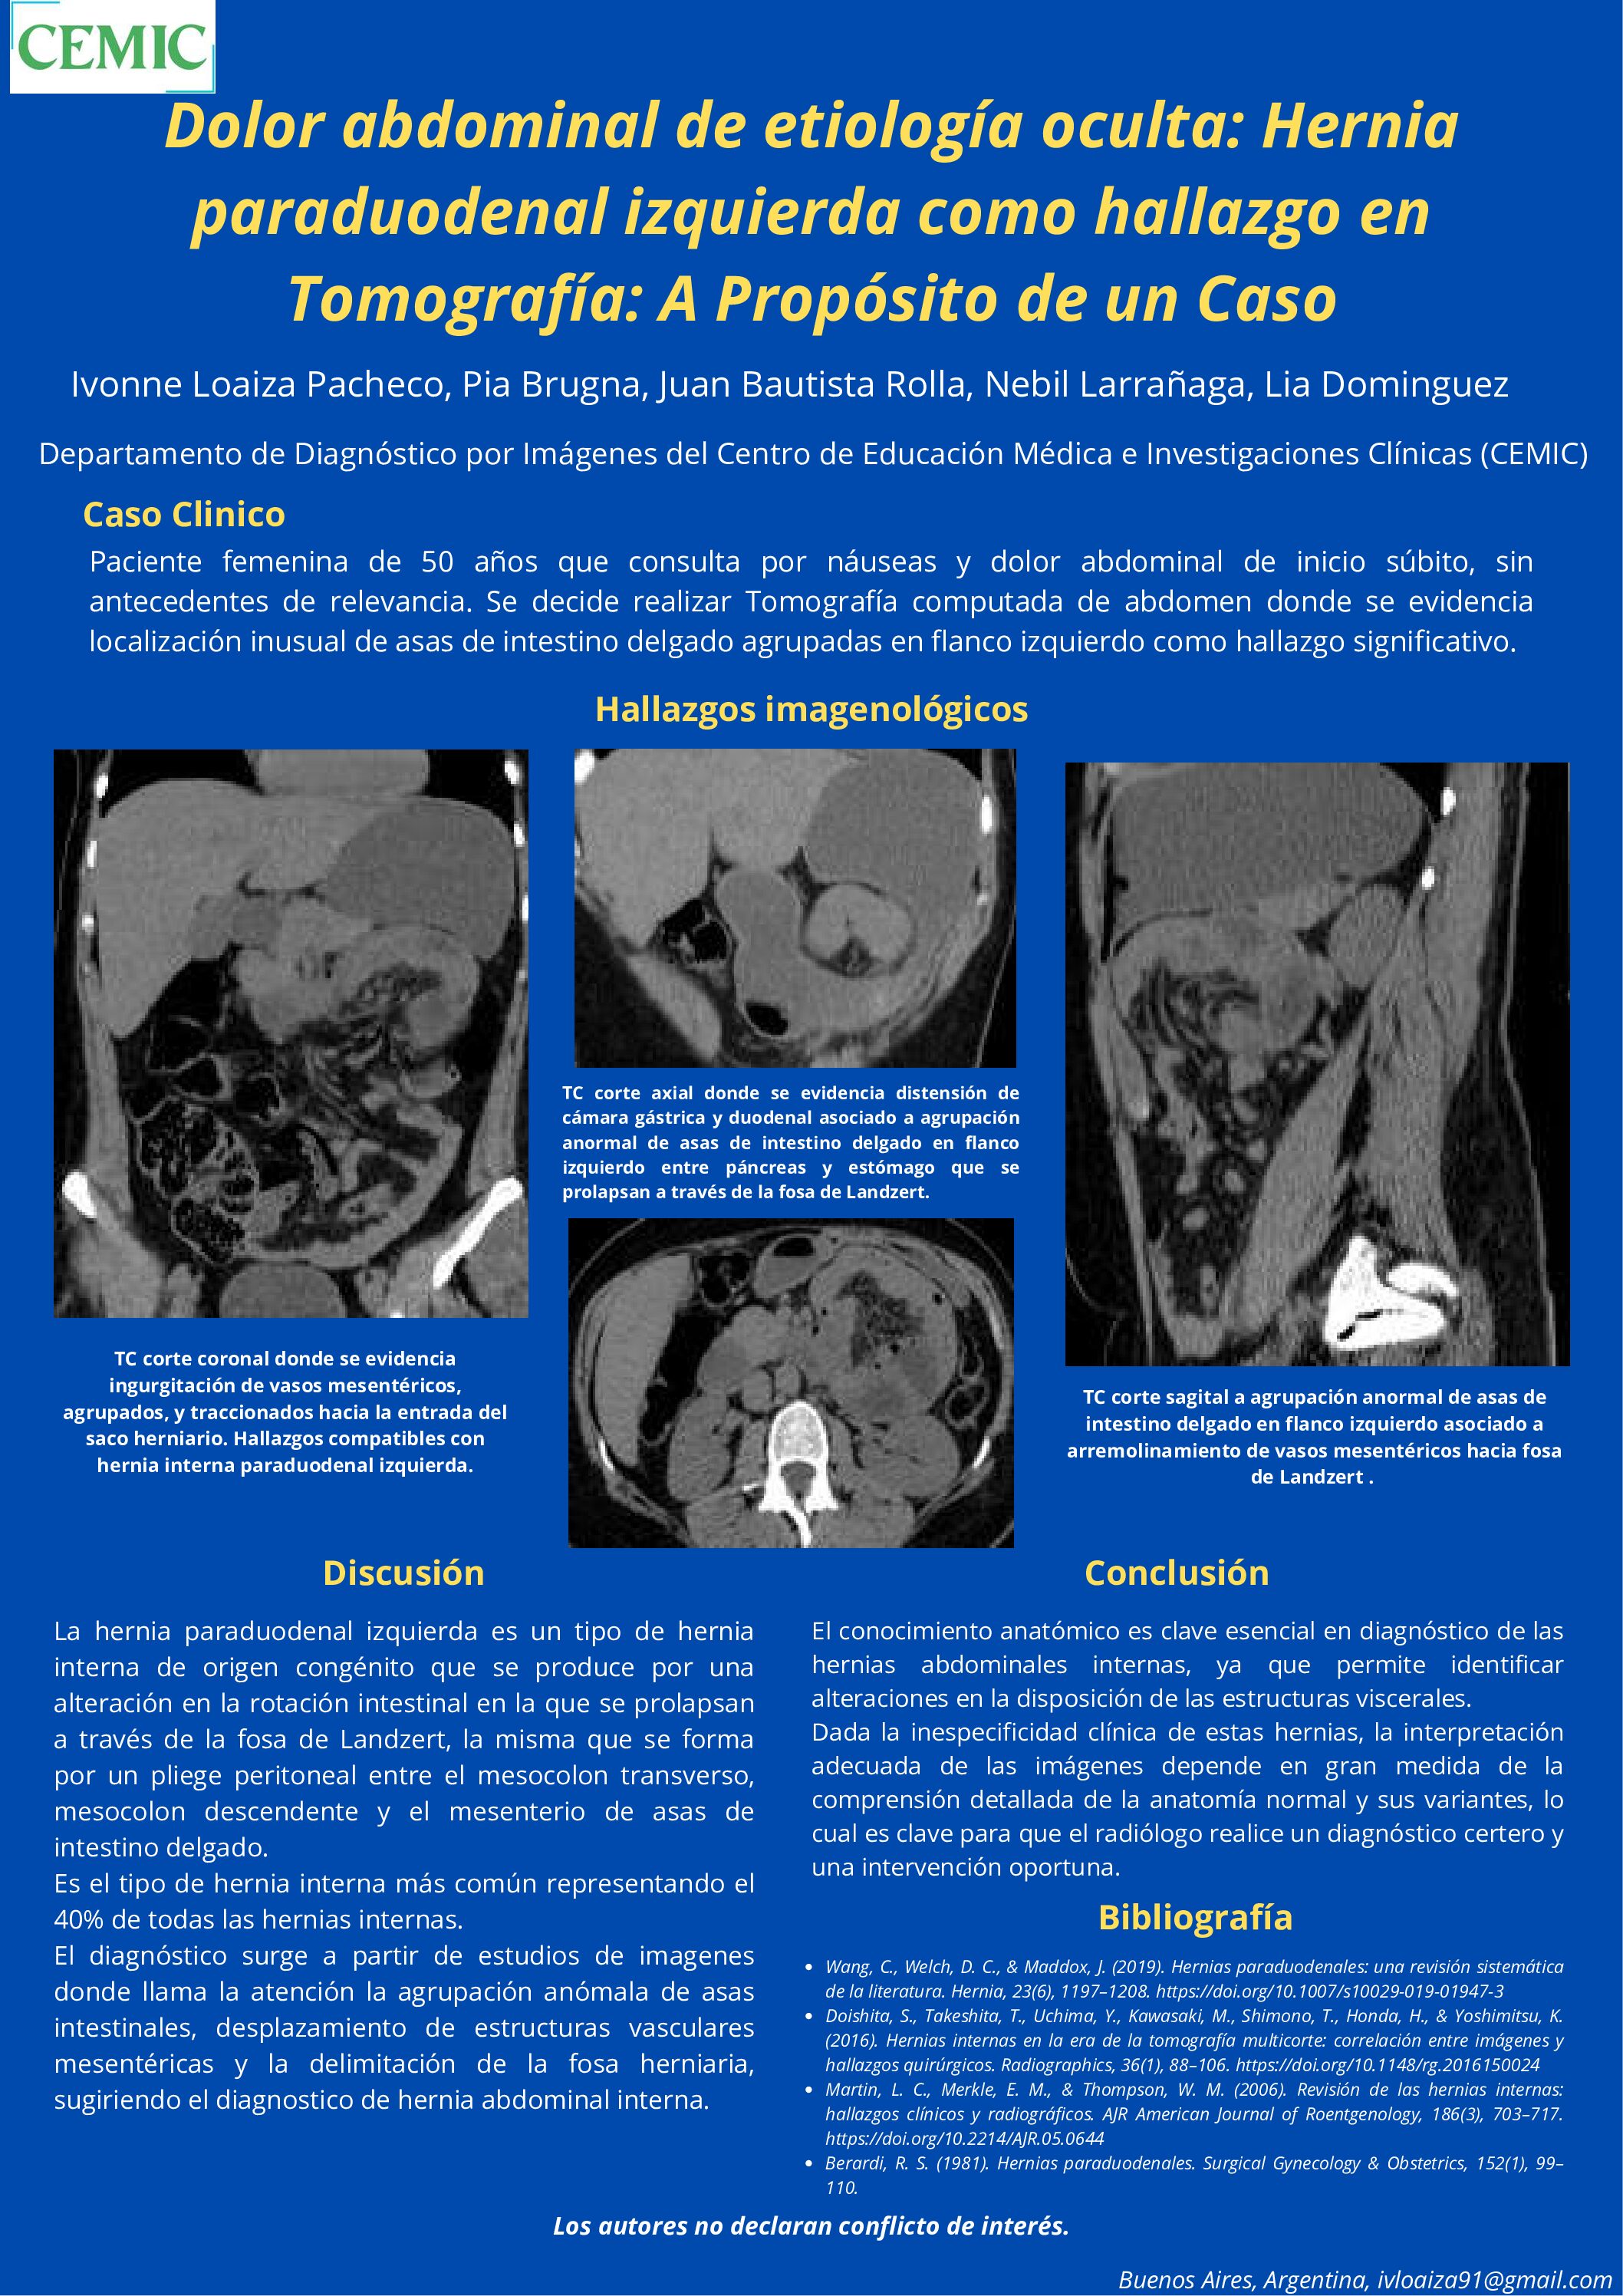

Dolor abdominal de etiología oculta: Hernia paraduodenal izquierda como hallazgo en Tomografía: A Propósito de un Caso

10/07/2025